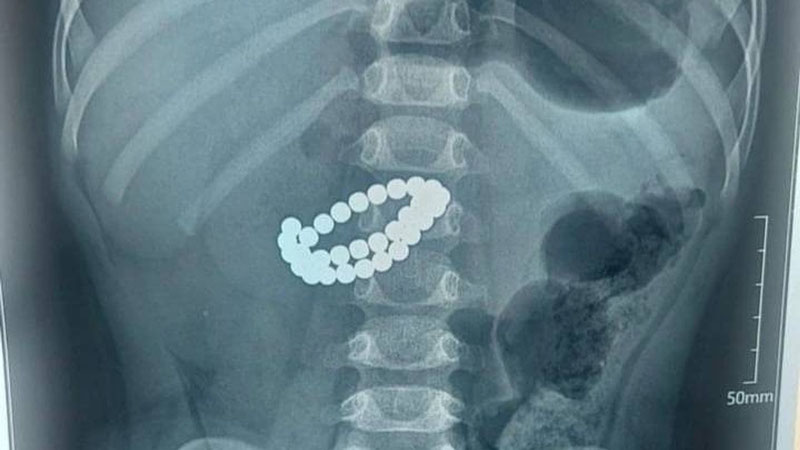

Ҳозирда ушбу ҳолат юзасидан Шаҳрихон тумани прокуратураси томонидан терговга қадар текширув ҳаракатлари олиб борилмоқда.